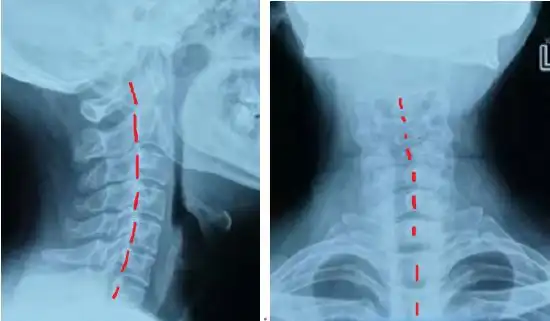

颈椎生理曲度变直了还能恢复吗(颈椎生理曲度变直严重吗)(3)

收藏丨手把手教你在x线上如何测量「颈椎生理曲度变直」

正经科普:如何判断自己颈椎是否弯了?